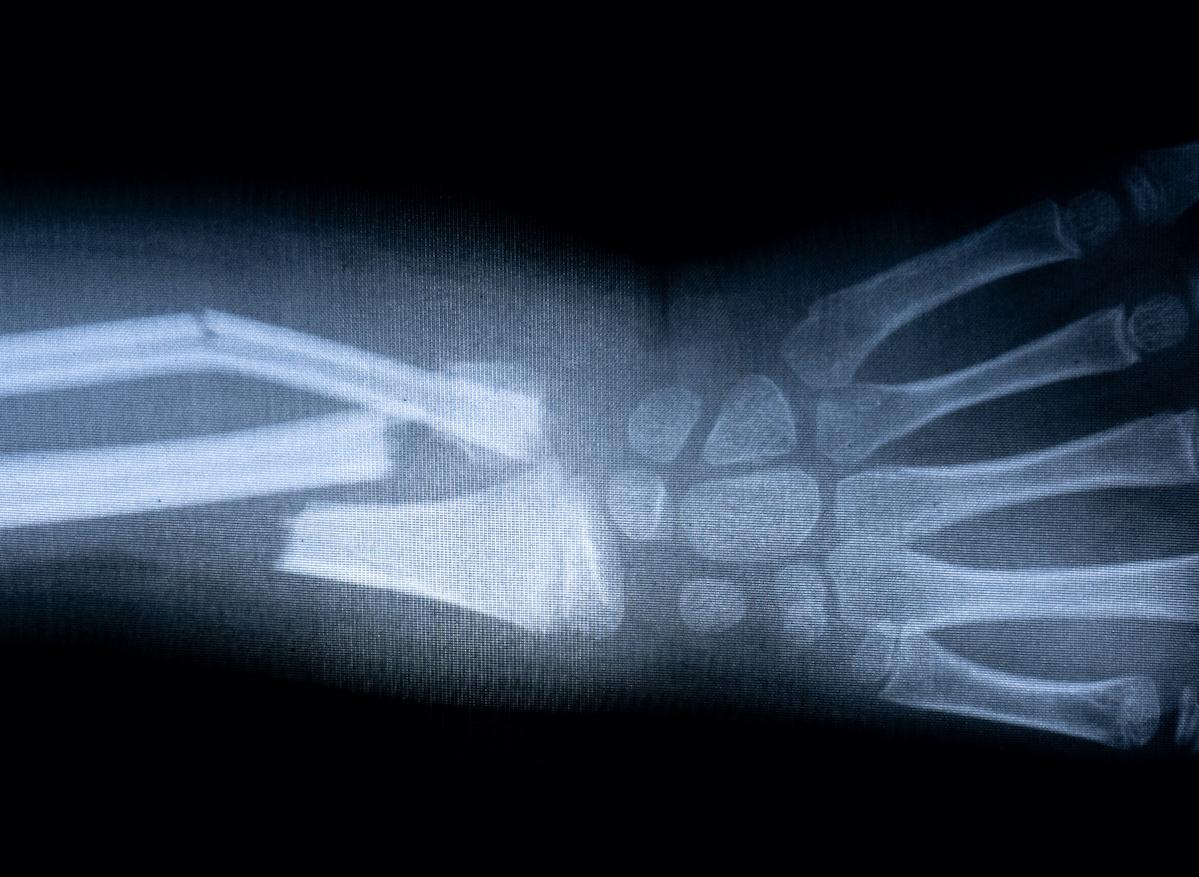

Les nouvelles technologies permettent de capturer de nouvelles images en temps réel de la formation des os et des dents. Une meilleure connaissance du processus qui permet d’envisager une accélération du processus de cicatrisation osseuse. Dans des travaux publiés le 18 novembre dans la revue Science Advances, des chercheurs américains de l’université de l’Illinois à Chicago ont décrypté avec une précision inégalée le processus par lequel les minéraux se combinent au niveau moléculaire pour former des os et d'autres tissus durs.

Les chercheurs ont capté des images en temps réel et à haute résolution du processus de minéralisation et sont parvenus à identifier les voies moléculaires précises qui forment les os et les dents. Jusque-là, les connaissances sur la formation des os étaient incomplètes, notamment au stade précoce d’organisation en structure des voies moléculaires. “Pour traiter les altérations osseuses ou surmonter les déficiences pathologiques de calcification, il est nécessaire de comprendre ces voies de minéralisation”, poursuit le Dr Rez Shahbazian-Yasser, professeur en génie mécanique à l’université de l’Illinois et auteur de l’étude.

L’étude a identifié in vitro les voies de minéralisation et de cristallisation de l'hydroxyapatite (HA), un minéral de la famille des phosphates, qui forme la base de nos tissus osseux. À l’aide d’une microscopie électronique à transmission dans une solution de salive artificielle, ils se sont rendus compte que la formation directe et indirecte de cristaux d'hydroxyapatite peut être obtenue en régulant la dissolution du phosphate de calcium. Une découverte qui est un grand pas vers un meilleur traitement des fractures osseuses mais aussi des maladies caractérisées par des déficiences de minéralisation, comme l'ostéoporose.

“En utilisant notre technologie, nous avons pu décrypter ces voies et mieux comprendre comment les particules d'hydroxyapatite se nucléent et se développent sur des modèles de phosphate de calcium, a détaillé le Dr Rez Shahbazian-Yasser. La compréhension de ce processus de cristallisation va nous permettre de développer de nouveaux médicaments pour accélérer la réparation osseuse des fractures ou pour traiter les caries dentaires.”

Ces découvertes permettent de reproduire ou accélérer le processus de biominéralisation pour la cicatrisation ou la régénération osseuse. “Notre étude fournit de nouvelles données claires sur la façon dont les minéraux s'organisent et se transforment en tissus osseux, et cette découverte a de nombreuses implications pour la cicatrisation des os ou des dents”, conclut le chercheur.